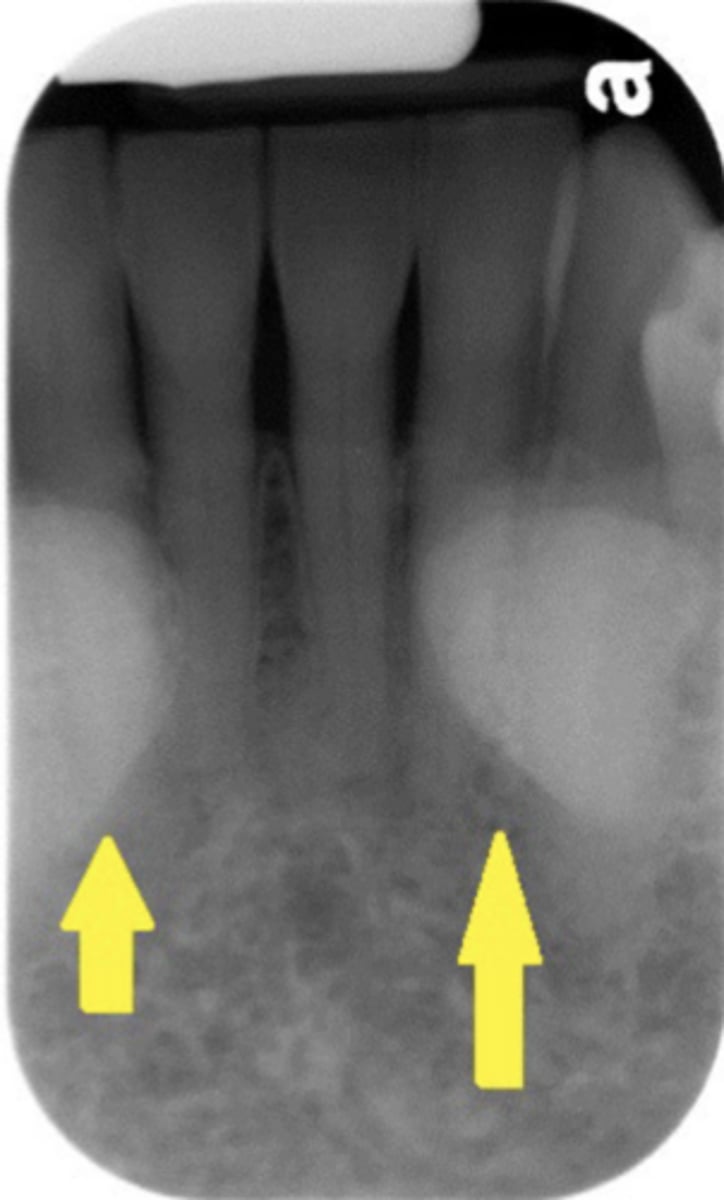

What is osteoporosis?

Systemic skeletal disease characterized by low bone mineral density and deterioration of bone microarchitecture

What radiographic changes are associated with osteoporosis?

Loss of trabecular architecture and thinning of mandibular cortical bone